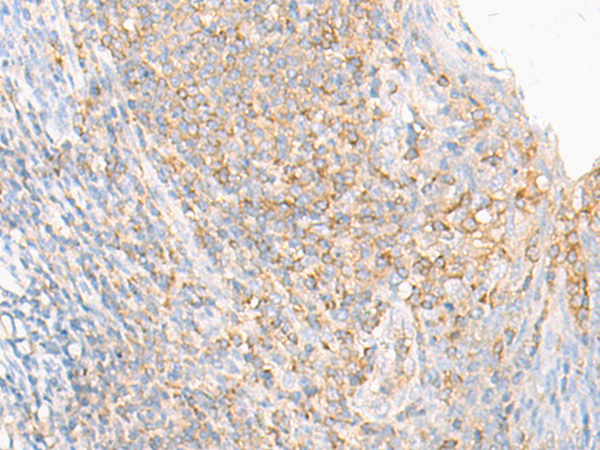

分类: 科研抗体货号: P06464别名: LRAP; L-RAP应用: IHC反应种属: Human